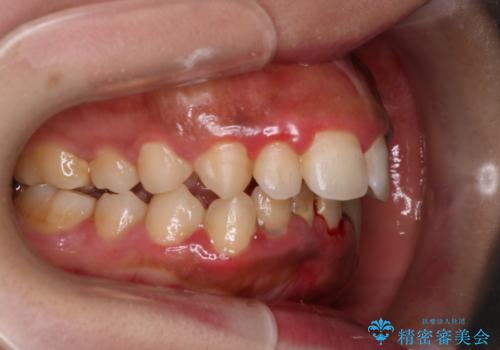

前歯の出っ張りとガタつきを改善

- 「前歯が出ていて並びも悪いのが気になる」との主訴で来院されました。診察の結果、上顎前歯の前突と中等度の叢生(ガタつき)が認められ、歯がきれいに並ぶスペースが不足していました。横顔のバランスと歯並びの両方を整えるため、上顎の左右の第一小臼歯2本を抜歯し、前歯を内側に下げながら歯列全体を整える治療計画を立てました。

治療はインビザラインによって進め、抜歯スペースを使って前歯を内側に引き込みながら、歯のガタつきも順に整えていきました。初期の段階で前歯の見た目が大きく変わり、患者さんにも「印象が柔らかくなった」と非常に喜んでいただけました。